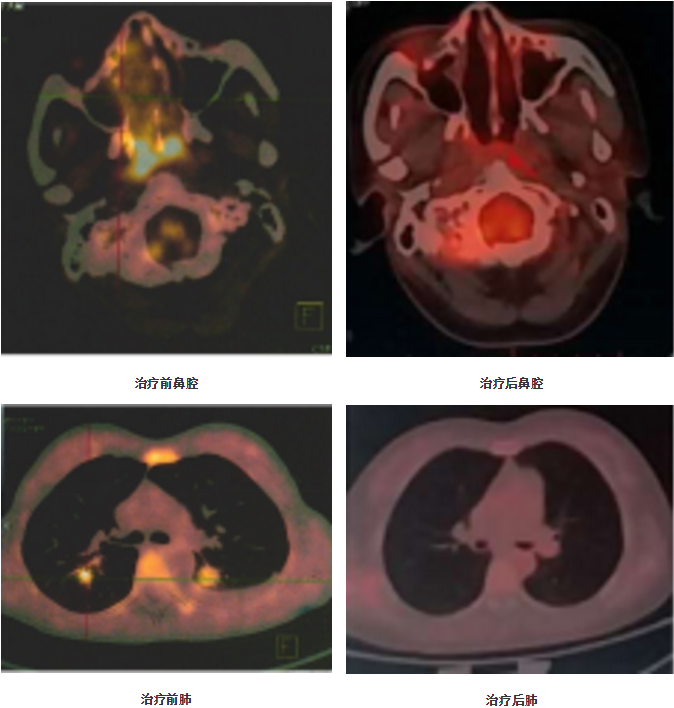

因病变范围广、肿瘤负荷大,第1次化疗选择LOP方案化疗后鼻堵及咽痛好转,咽部溃疡愈合,腹部皮下结节缩小,治疗有效。此后完成3次基于培门冬酶的强化疗方案,每21天一周期。2次化疗后鼻咽MRI未发现明显异常软组织影,拔除气管套管。4次化疗后PET/CT:鼻腔、鼻咽顶后壁、咽淋巴环及右侧筛窦软组织影范围明显缩小且SUVmax9.3;右颈后间隙、颈动脉鞘周围及颌下淋巴结明显缩小或消失,放射性摄取基本恢复正常;余病灶消失,考虑PR,继续完成2次化疗,末次化疗时间2020.2.20(共6次化疗)。建议患者行自体造血干细胞移植巩固,患者及家属拒绝。2020.5.18 当地PET/CT提示完全缓解。下一步考虑免疫治疗维持。